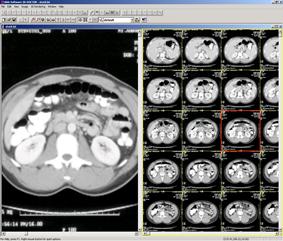

Рис. 21. Магнитно-резонансная томография